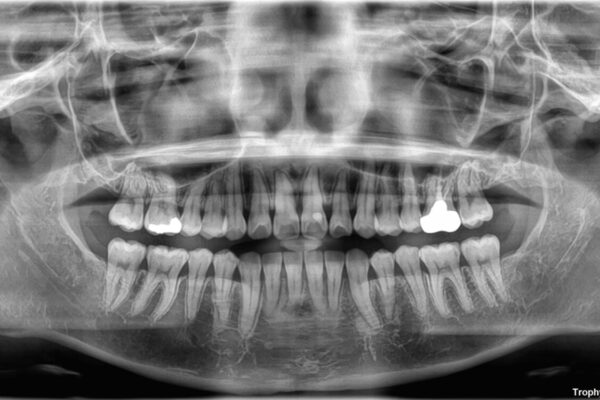

診察の結果、上下の前歯部に**叢生(そうせい/歯のガタガタ・重なり)**が認められました。

特に上の前歯にはねじれや重なりがあり、審美的にも清掃性にも影響している状態でした。

また、上顎前歯の重なっていた部分にはむし歯が見つかり、治療中に適切な処置を行っています。

治療前

• 前歯のねじれ・ガタガタを10か月で改善!20代女性の矯正治療|クリアブラケットでむし歯になりにくい歯並びへ改善 治療前画像